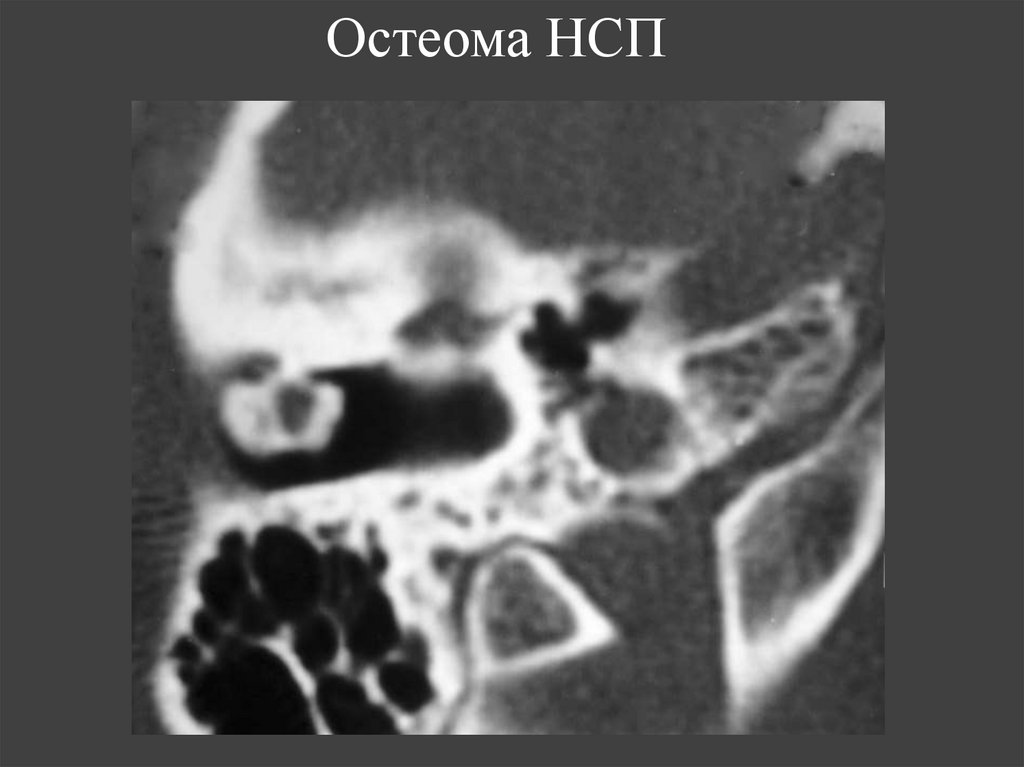

75. Остеома НСП